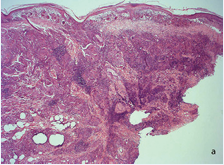

Biopsy of the anterior thorax showed a dermal infiltrate rich in giant cells and lymphocytes that touched the epidermis and compromised all the dermis and the hypodermis (Figure 2).

Figure 2a Skin biopsy of the trunk. Panoramic view showing granulomatous infiltration of dermis and hypodermis with abundant giant cells and lymphocytes.

Figure 2b Sub epidermal granulomas rich in giant cells with lymphocytes, some of which penetrate the basal epidermis.

Figure 2c A giant cell of the infiltrate has numerous nuclei, is surrounded by mononuclear cells and has several lymphocytes in its cytoplasm (emperipolesis). A-C: HE. A, 2.5X B, 10 X. C, 40X..